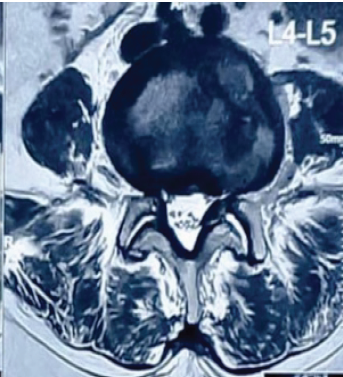

Traumatic Durotomy with Entrapment of Nerve Roots in a Lumbar Burst Fracture Diagnosed Intraoperatively: A Case Report

Dileepan Chakrawarthi , Harish K Nagappa , S Sivamurugan